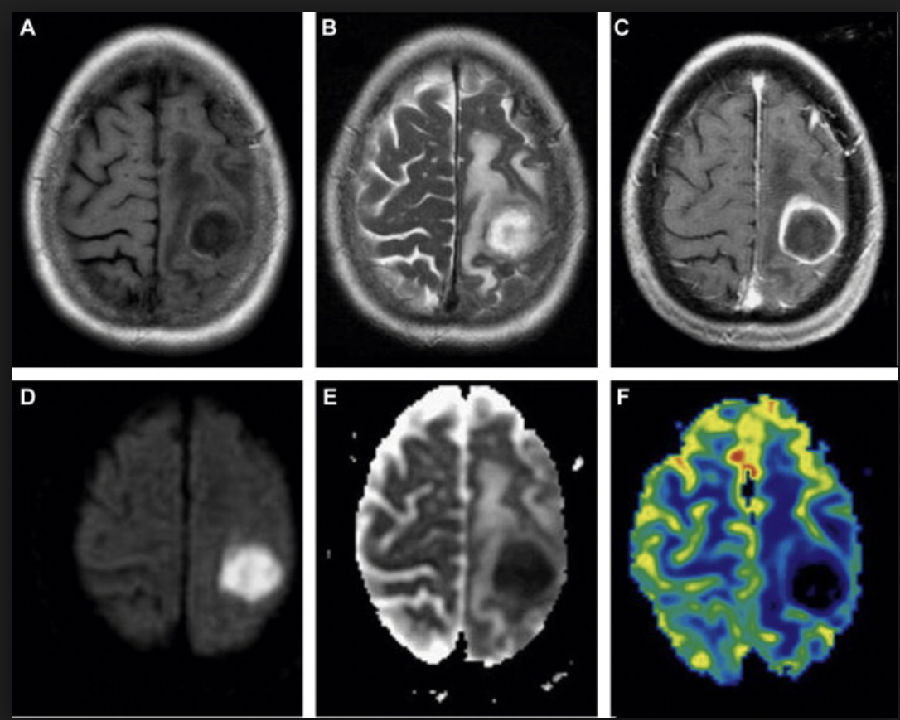

图2

图2 脑脓肿